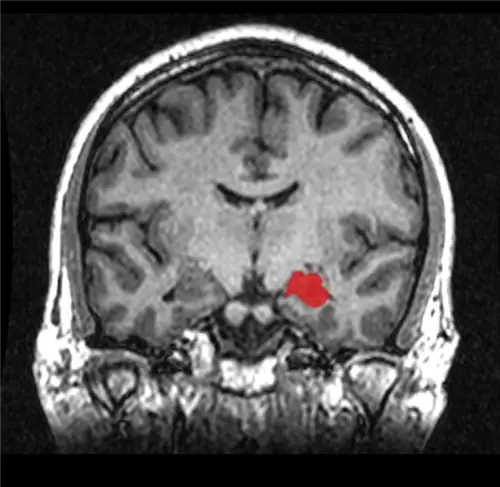

Исследователи из Северо-Западного университета изучили работу мозга у людей и мышей, живущих с хронической болью. Во-первых, они изучили различия в психическом функционировании у людей, живущих с хронической болью и без нее. Используя сканирование мозга, исследователи обнаружили, что у людей с длительной болью, такой как боль в спине (которая определяется как длительность более шести месяцев), были обнаружены признаки сокращения гиппокампа. Это важно, потому что гиппокамп - это область серого вещества в мозгу, отвечающая за обучение и память. На изображении ниже он выделен красным цветом:

Изображение